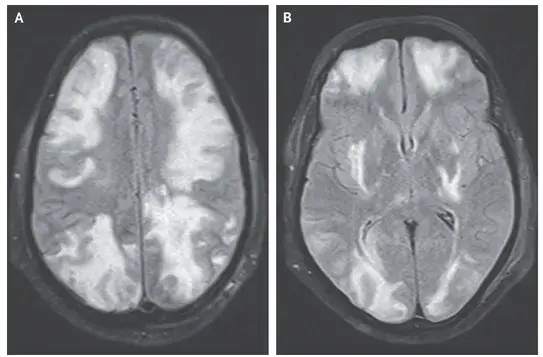

A ressonância magnética (MRI) de crânio ponderada em T2 mostrou sinal hiperintenso na substância branca cortical e subcortical, achados consistentes com **edema vasogênico** (imagens A e B). Os achados da angio-RM arterial e venosa foram normais.

Foi feito o diagnóstico de síndrome de encefalopatia posterior reversível (PRES) devido ao **uso de ciclosporina.**

**Dicas importantes**: Apesar do nome da síndrome, a PRES não afeta apenas as partes posteriores do cérebro. Não esquecer que pode estar associada à **hipertensão**, **encefalopatia urêmica, eclampsia** ou **terapia imunossupressora**, como foi o caso deste paciente.

Realizado retirada do medicamento (ciclosporina) e os sintomas do paciente e os achados da ressonância magnética foram resolvidos (Imagem C).